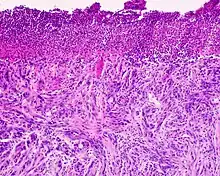

Desmoplastic melanoma is a rare cutaneous condition characterized by a deeply infiltrating type of melanoma[2]:696 with an abundance of fibrous matrix.[3] It usually occurs in the head and neck region of older people with sun-damaged skin.[3] Diagnosis can be difficult as it has a similar appearance to sclerosing melanocytic nevi as well as some nonmelanocytic skin lesions such as scars, fibromas, or cysts.[3]